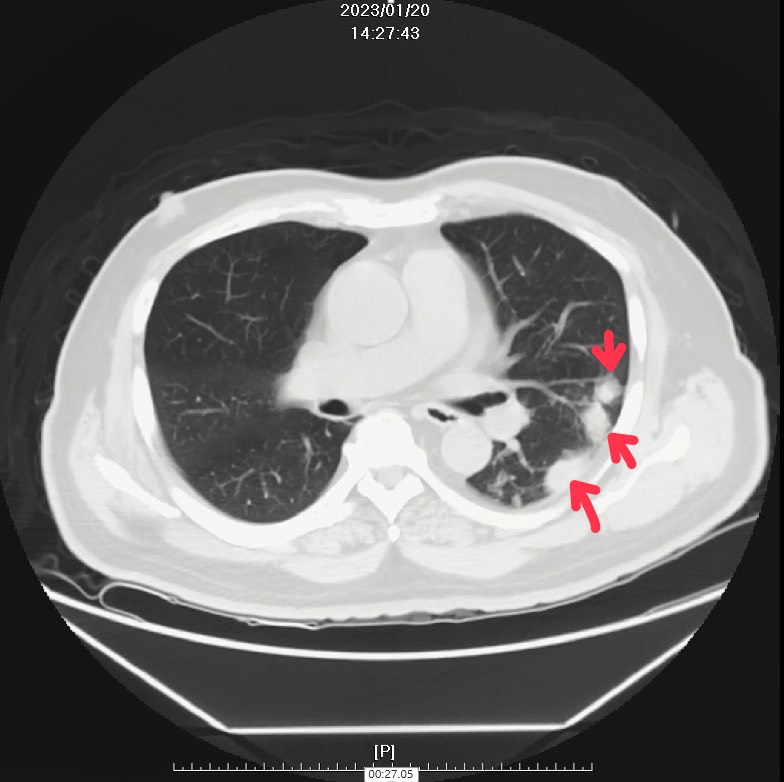

68歲蔡先生因身體不適就醫,檢查發現肺部有多個結節,先後接受肺癌與肺結核治療,病情未見好轉。經由臺中榮總胸腔部呼吸感染免疫科團隊評估,注意到他不咳不喘、症狀表現非典型,分枝桿菌中心與胸腔外科團隊審慎評估後,建議胸腔外科團隊手術切除病灶取得組織檢體。檢驗確認為肺部隱球菌感染(Pulmonary cryptococcosis),經抗真菌藥物治療後,病情明顯改善。

臺中榮總分枝桿菌中心團隊解釋,民眾進行胸部X光或電腦斷層檢查時,常見肺部有一些小小的「陰影」,這些就是肺結節,指的是肺臟內直徑小於3公分的病灶,常見的原因包括惡性腫瘤、良性腫瘤、感染或血管異常,重點是依照醫師建議進行評估與追蹤,精確診斷結節的原因,避免不必要的擔憂。